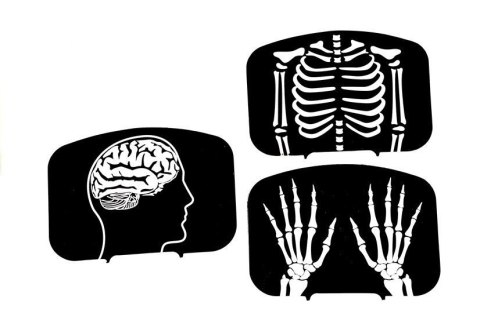

- zdjęcia rentgenowskie głowy, klatki piersiowej, kończyn górnych